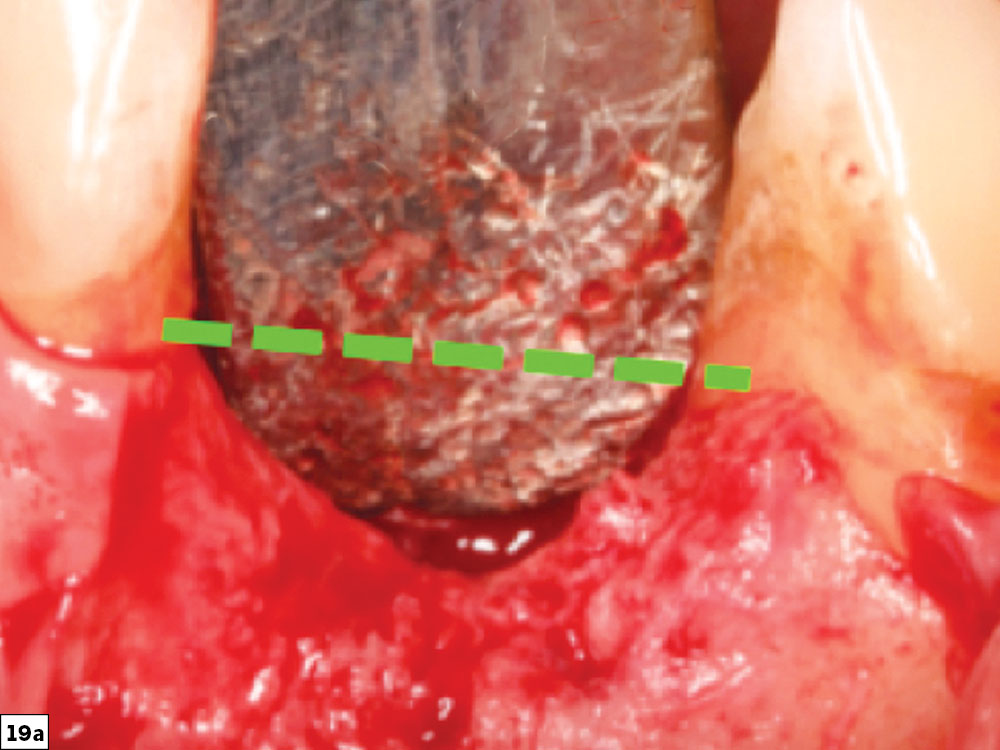

Vertical defect close-up

Horizontal and vertical bone growth to the level of adjacent teeth

Figures 19a, 19b: Very challenging vertical defect (19a) and final post-healing image depicting horizontal and vertical bone growth to the level of the adjacent teeth (19b).